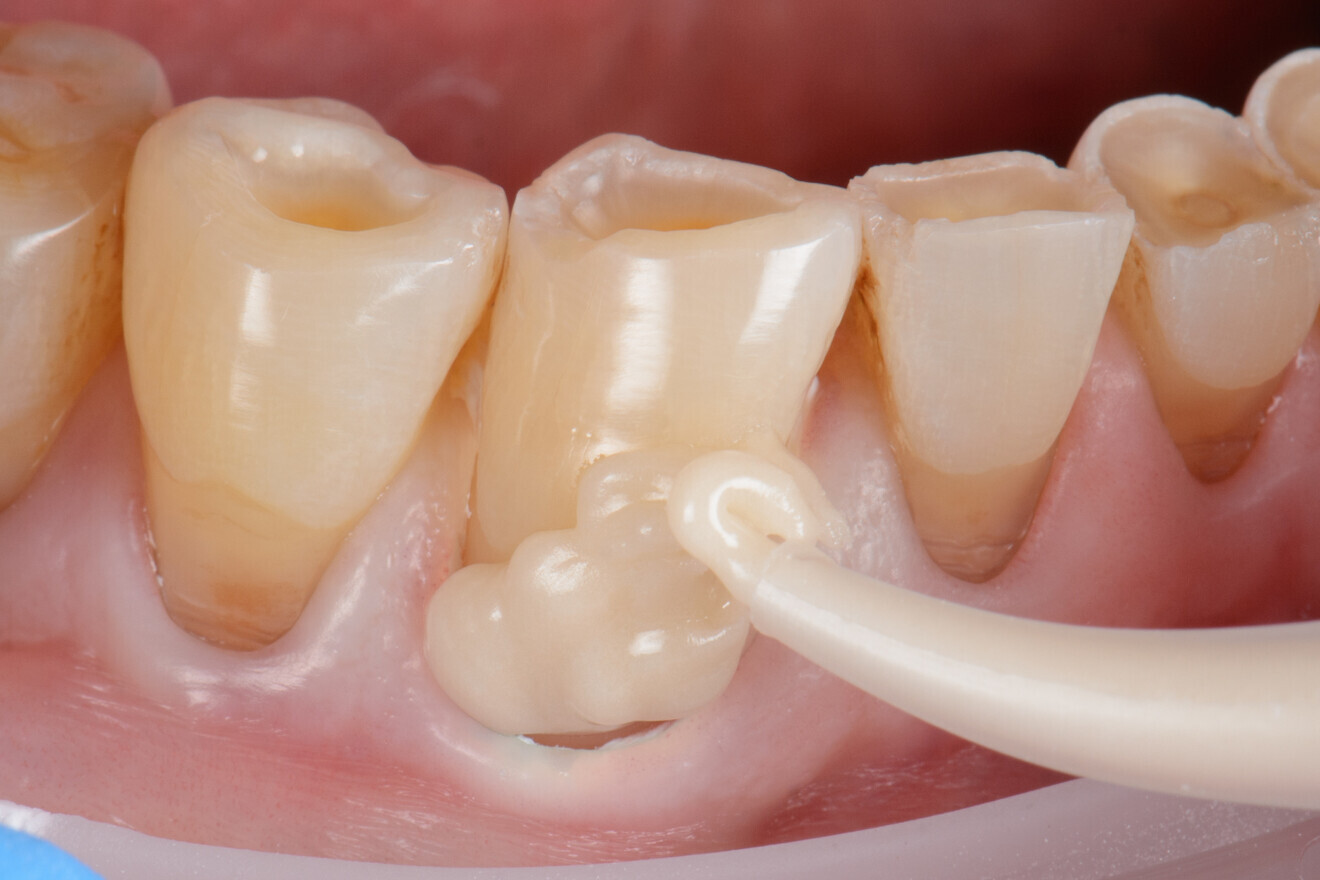

Alors que seules les dernières générations de ciments verres ionomères (CVI) sont de plus en plus utilisées pour restaurer les cavités soumises aux contraintes, cette classe de matériaux a toujours été une solution valable pour les lésions cervicales (car les problèmes liés à l’abrasion et aux contraintes sont moins importants qu’au niveau des surfaces occlusales et proximales). Les verres ionomères modifiés par adjonction de résine ont tout particulièrement montré un taux de survie élevé dans les lésions cervicales (il convient toutefois de noter que de nombreuses études les évaluaient dans des lésions non carieuses). La dernière génération de matériaux, dénommée verres hybrides (Fig. 3), se caractérise par une grande stabilité à l’abrasion et à l’érosion, et par une meilleure résistance à la flexion. Ces propriétés sont dues à des modifications de la composition chimique du matériau, principalement à l’ajout d’une phase vitreuse constituée de particules plus petites et de chaînes d’acide acrylique plus longues.

Fig. 3a : Une lésion cervicale est restaurée au moyen d’un verre hybride. a) Mise en place d’EQUIA Forte HT,

Fig. 3b : EQUIA Forte Coat crée une surface lisse,

Fig. 3c : restauration après la finition (avec l’aimable autorisation du Dr Javia Tapia Guadix, Espagne).

Une étape supplémentaire de revêtement avec une nanorésine donne à la surface de verre un aspect plus lisse et esthétique. Plusieurs études menées en laboratoire ont confirmé que les verres hybrides présentent en effet des propriétés nettement supérieures à celles de leurs prédécesseurs, tout en continuant à offrir les mêmes avantages, c’est-à-dire la facilité de la mise en place et la bioactivité, en particulier la libération de fluorure – un aspect pertinent pour la protection contre les caries radiculaires secondaires. D’autres études ont démontré que les CVI réduisent le risque carieux au niveau des limites marginales de la restauration sur une distance allant jusqu’à 300 μm. Une zone intermédiaire résistante aux acides, constituée de calcium dissous provenant des tissus dentaires et du fluor libéré par le matériau, est en outre susceptible d’augmenter la résistance contre les lésions secondaires.8